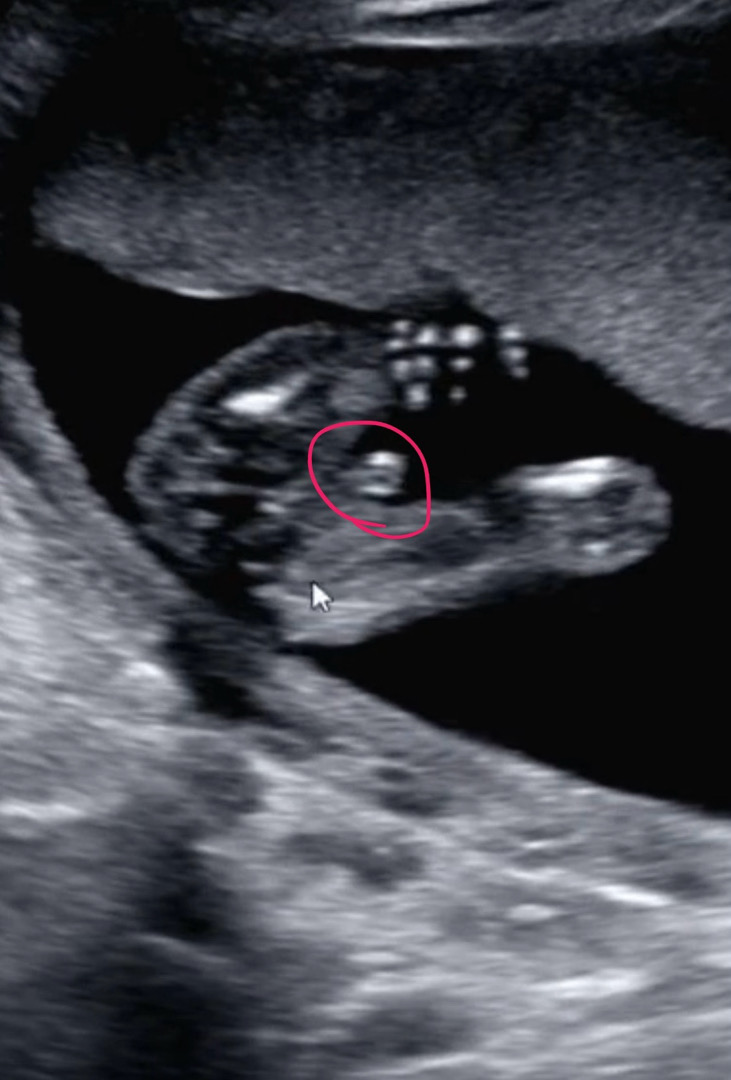

16์ฃผ 2์ฐจ ๊ธฐํ์ ๊ฒ์ฌ ํ๊ณ ์์ด์ ^^ ๋ค๋ฆฌ์ฌ์ด ํํ ๊ณ ํ ๋ง์ง์?? ใ ใ ใ ใ ใ ใ ๊ฐํน ๋ธ์ด์ฌ๋ ์ด๋ ๊ฒ ๋ณด์ฌ ๋ค์ด๊ฐ๋ค๊ณ ํ๋๋ฐ ๋ค์ด๊ฐ์ง ์๊ฒ ์ฃ ?? ใ ใ

์ ๊ฐ ์์ง ๋ชฐ๋ผ์ ๊ถ๊ธํด์ ๊ทธ๋ฌ๋๋ฐ์ ~ ใ 0ใ ์ ์ด์ํ ํํ๊ฐ ์ง๊ธ ์๋ฉ์ด ๋ฐ ๋ถ๋ถ์ธ๊ฑฐ์ฃต?? ๋๋ค๋ฆฌ ์ธ๊ฑฐ๊ตฌ์ ??